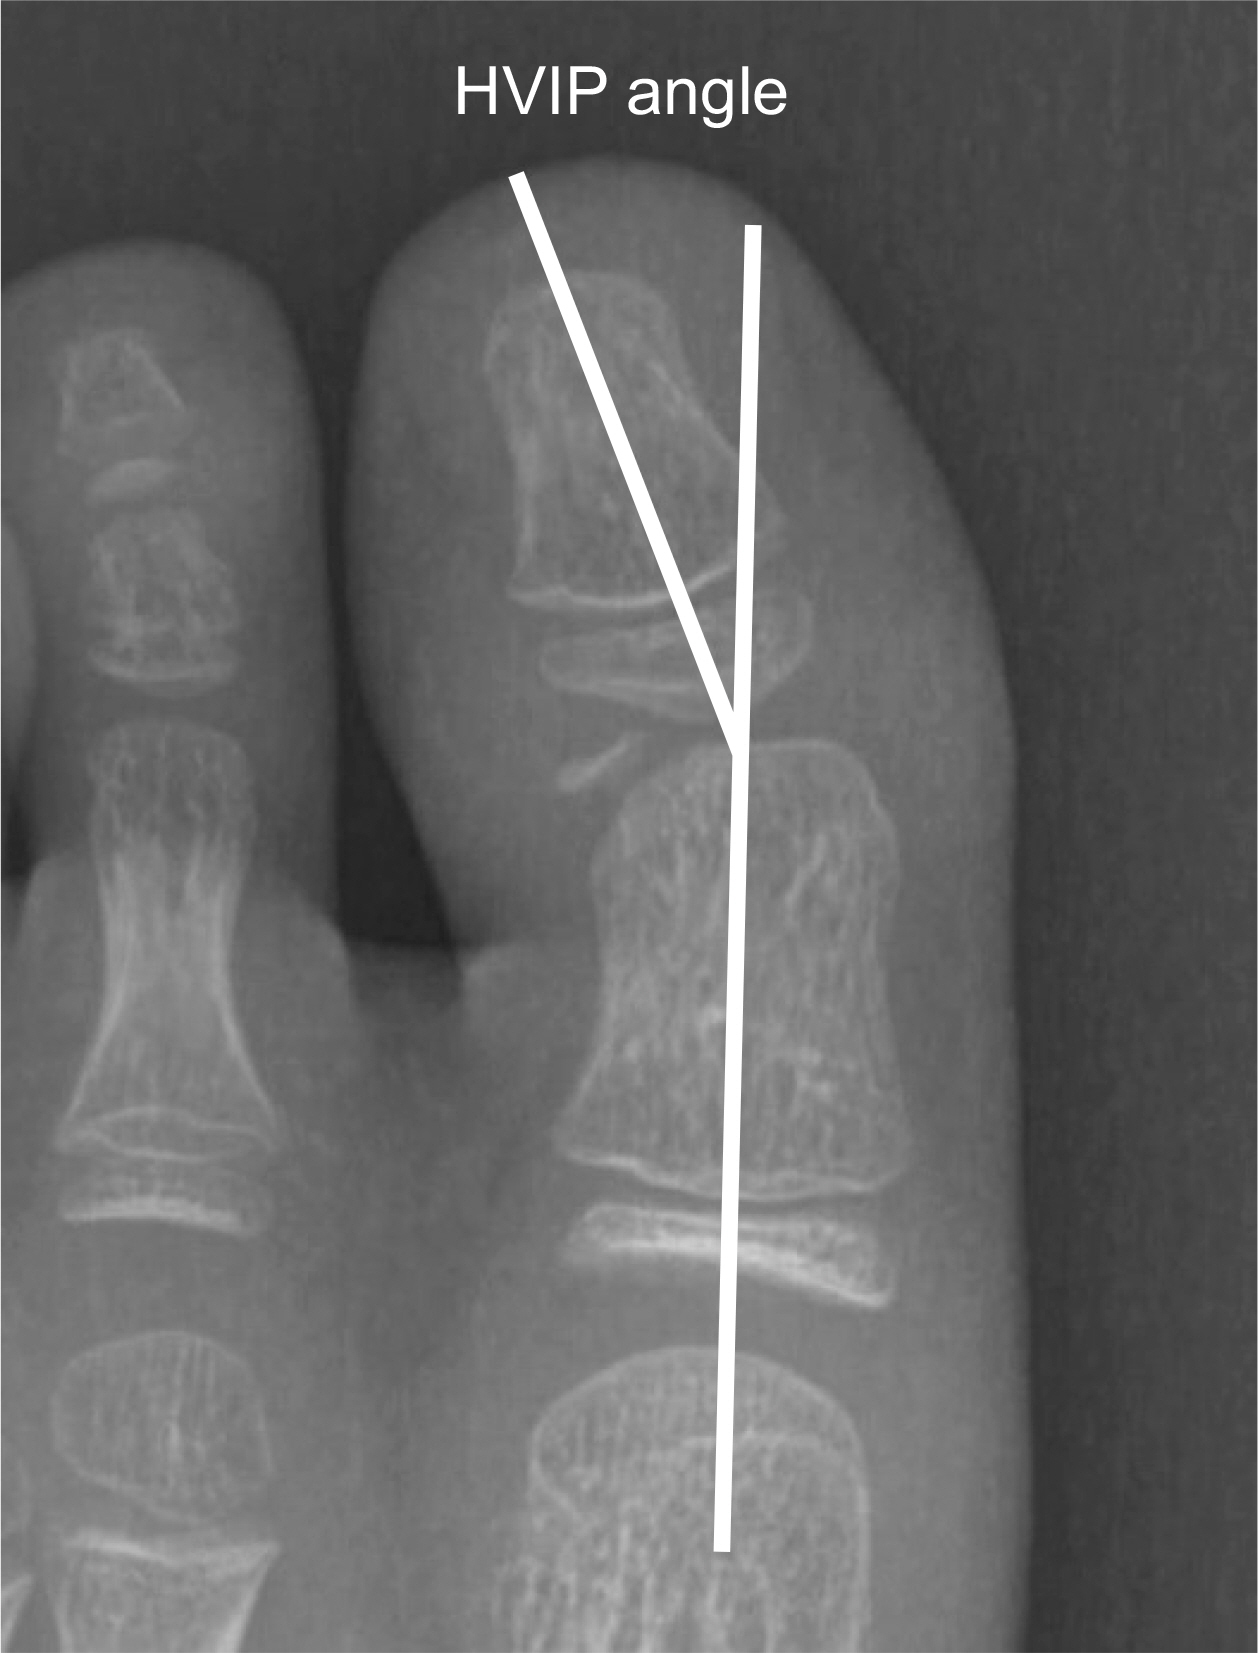

Fig. 1.

Measurement of the hallux valgus interphalangeus (HVIP) angle.

The study retrospectively reviewed all the patients who were diagnosed as intra-articular proximal phalangeal head fracture of the big toe and who underwent surgical intervention in our institution. The size of the bony fragment and hallux valgus interphalangeus angle were measured on the preoperative X-rays. The size and rotation of the osteochondral fragment, the presence of avascular necrosis, ligamentous injury and soft tissue entrapment were assessed on the preoperative magnetic resonance images (MRIs). The radiologic and functional evaluation were performed at 1 year postoperatively.

The average size of the bony fragments measured on the X-rays was 4.1 mm in width and 2.3 mm in length. Two cases showed hallux valgus interphalangeus. Preoperative MRI was performed in four cases and the average size of any osteochondral lesion was 5.3 mm in width, 3.9 mm in length, and 4.7 mm in height. Rotation of the osteochondral fragment was observed in one patient, and soft tissue entrapment was noted in two patients. Postoperatively, successful bony union was achieved in all the patients and the average time to union was 74.4 days.